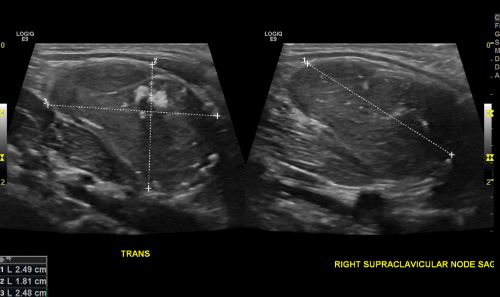

الأشعة فوق الصوتية لسرطان الطفولة كلنا معا